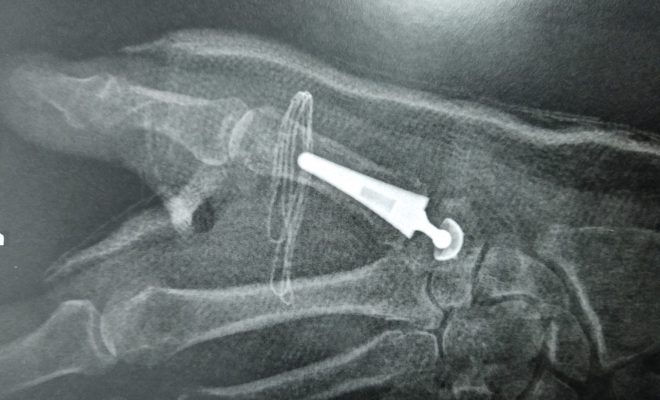

1er Prothèse pour arthrose du pouce à la Clinique Saint Charles

C’est donc avec plaisir que j’ai réalisé en ce mois de Mars 2021, la première prothèse de pouce de l’établissement et ainsi pu faire profiter à cette patiente de mon expérience sur cette pathologie.